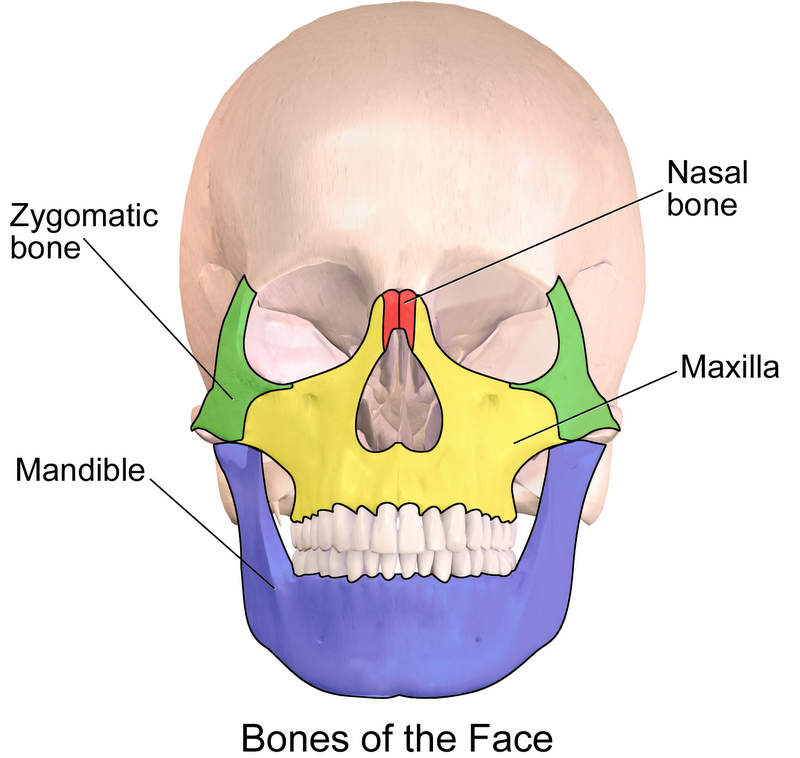

The four main bones in the fact are:

- Zygomatic bone

- Mandible

- Maxilla

- Nasal Bone (Nose)